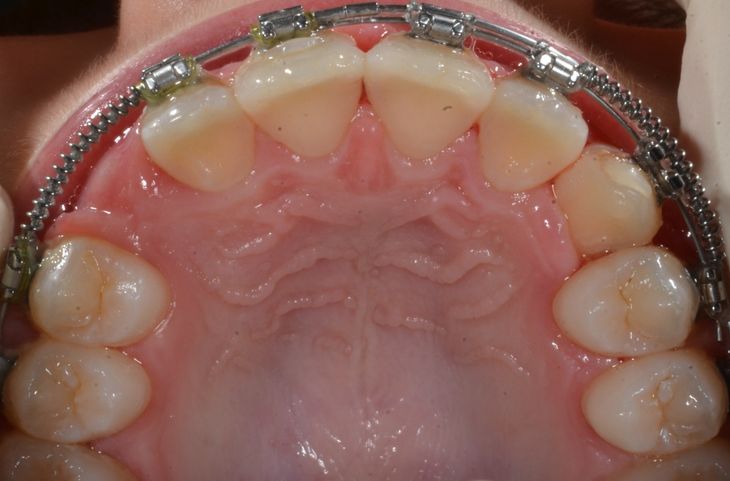

Alcuni casi dello Studio